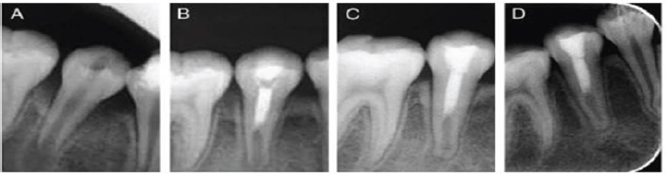

Figure 11: Revitalization procedure.

a) Preoperative radiograph with periapical lesion and open apex.

b) After 3 months elongation with periapical lesion and open apex.

c) After 8 months shows narrowing if apex and thickening of dentine walls.

d) After 18 months shows healing of lesion and apical closure.